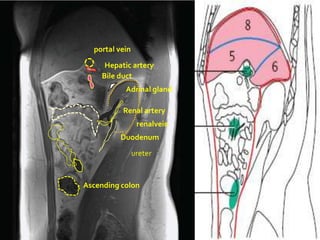

portal vein

Hepatic artery

Bile duct

Adrinal gland

Renal artery

renalvein

Duodenum

ureter

Ascending colon